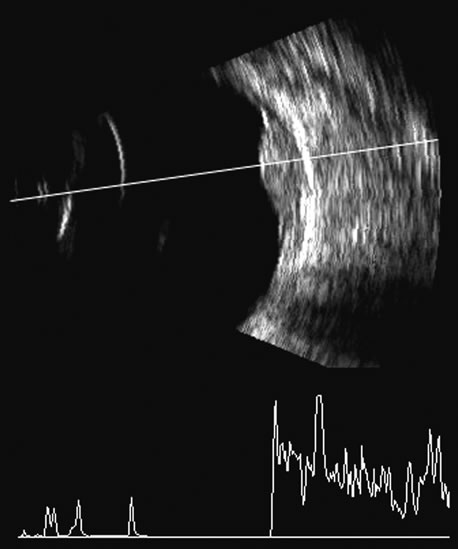

Fig. 22. Some hemangiomas and metastatic carcinomas may simulate a melanoma. They are differentiated on the basis of a very high amplitude internal echo complex for the hemangioma, a moderately low but sustained echo pattern for the metastasis, and an A-scan with decreasing reflectance as the tumor thickness is traversed. In the center scan of a melanoma, note the double anterior layer caused by edema fluid underlying the crest of the melanoma (arrow).